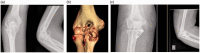

Background: Elbow fracture dislocations are complex injuries that can provide a challenge for experienced surgeons. Current classifications fail to provide a comprehensive system that encompasses all of the elements and patterns seen in elbow fracture dislocations.

Methods: The commonly used elbow fracture dislocation classifications are reviewed and the three-column concept of elbow fracture dislocation is described. This concept is applied to the currently recognised injury patterns and the literature on management algorithms.

Results: Current elbow fracture dislocation classification systems only describe one element of the injury, or only include one pattern of elbow fracture dislocation. A new comprehensive classification system based on the three-column concept of elbow fracture dislocation is presented with a suggested algorithm for managing each injury pattern.

Discussion: The three-column concept may improve understanding of injury patterns and treatment and leads to a comprehensive classification of elbow fracture dislocations with algorithms to guide treatment.